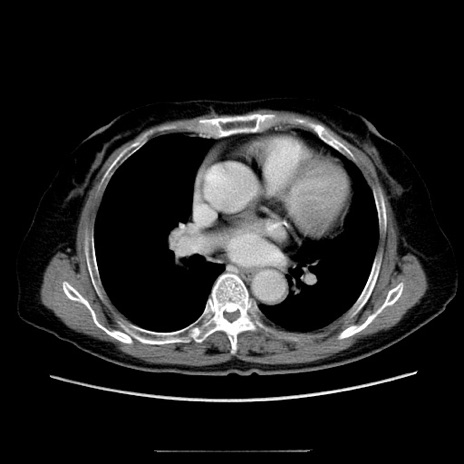

症例5(横断像)

【症例】70歳代女性

【主訴】お腹が張る

【現病歴】1週間くらい前から腹部膨満の自覚あり。昨日夜から増悪したため、本日救急外来受診。

【身体所見】意識清明、BT 36.5℃、BP 165/106mmHg、HR 80bpm、SpO2 98%、腹部:膨満、軟、自発痛・圧痛なし、触診にて不快感あり、腸蠕動音:減弱

【データ】WBC 12600、CRP 1.04